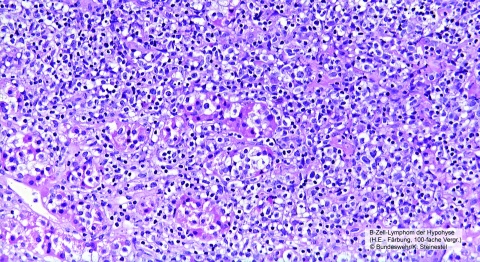

Wir präsentieren die seltene Manifestation eines diffus-großzelligen-B-Zell Lymphoms (DLBCL) im vorderen Anteil der Hypophyse. Bei initialer Präsentation bestand ein partieller Hypopituarismus und eine inkomplette Okulomotoriusparese. Unter dem Verdacht eines Hypophysenmakroadenoms wurde eine transsphenoidale Resektion durchgeführt. Die anschließende histopathologische Begutachtung brachte das Ergebnis eines malignen Lymphoms hervor. Die Immunchemotherapie mittels R-CHOP (Rituximab, Cyclophosphamid, Doxorubicin, Vincristin, Prednisolon) führte zu einer kompletten Remission.

Die Analyse der vorliegenden Literatur konnte insgesamt 36 Fälle von Non-Hodgkin-Lymphomen der Hypophyse identifizieren. Der Nicht-Keimzentrums (non-GCB oder ABC)-Typ eines DLBCL gemäß der Hans-Klassifikation kommt etwas häufiger vor als der Keimzentrums- GCB-Typ. Eine visuelle Störung, hervorgerufen durch eine Kompression des Chiasma opticum oder des Nervus opticus, oder endokrinologische Störungen der Adenohypophyse, mit oder ohne Auftreten eines Diabetes insipidus, gehören zu den am häufigsten dokumentierten Symptomen bei diesen Patienten.